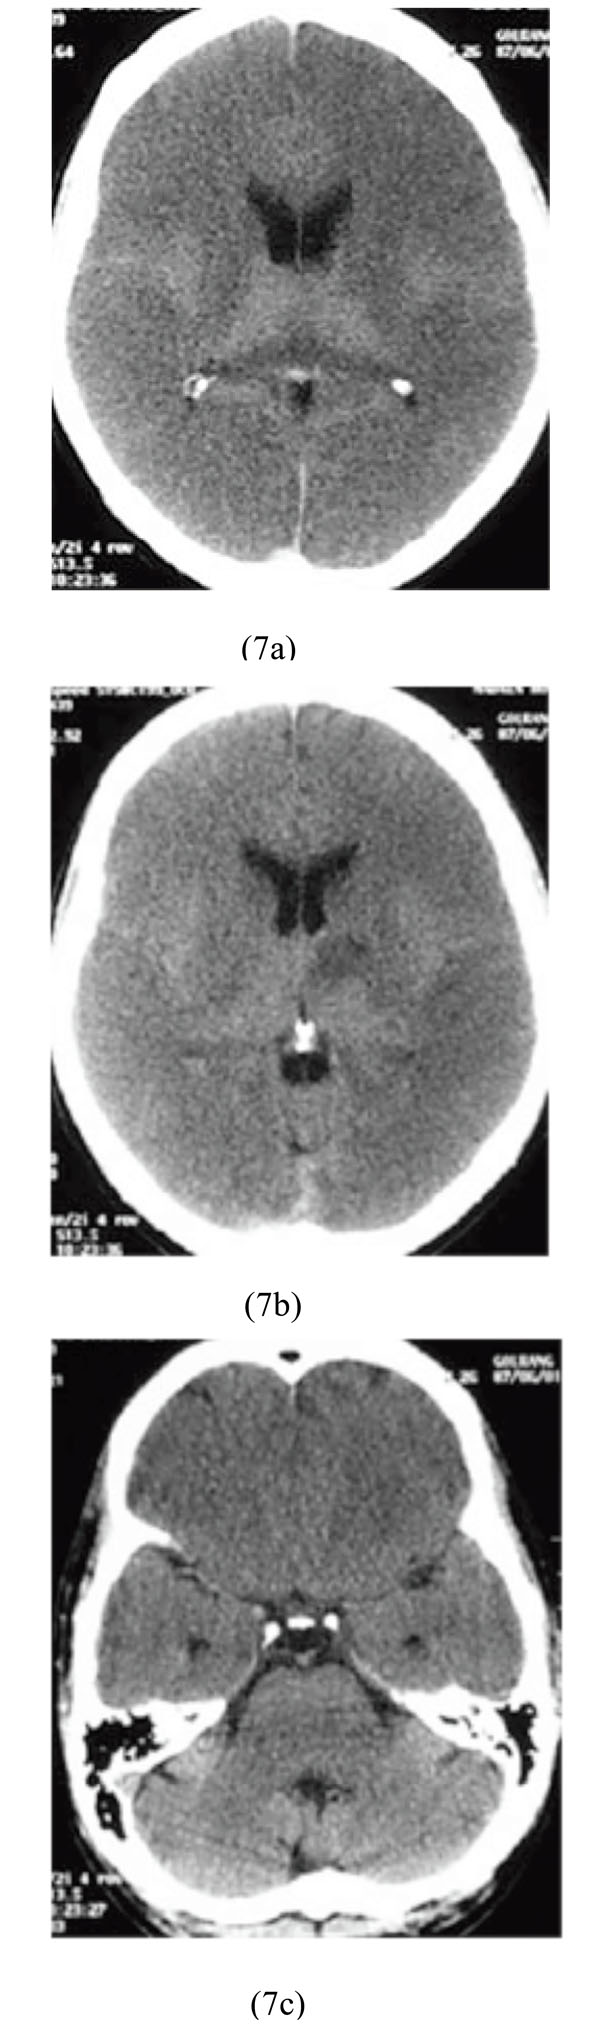

A 26-year-old crack (purer form of heroin) abuser man was admitted to our hospital. Physical examination showed: BP=110/70, PR=90/min, and RR=16/min. Brain CT scan showed massive supratentorial cytotoxic edema and pseudosubarachnoid hemorrhage sign as obviously reversed gray and white matter differentiation with sparing of infratentorial region. Also, a focus of hypodensity involving the left basal ganglia was observed (Figs. 7a-7c).

Massive supratentorial cytotoxic edema and pseudosubarachnoid hemorrhage sign with sparing of infratentorial region along with left basal ganglia. hypodensity after poisoning with crack (heroin).